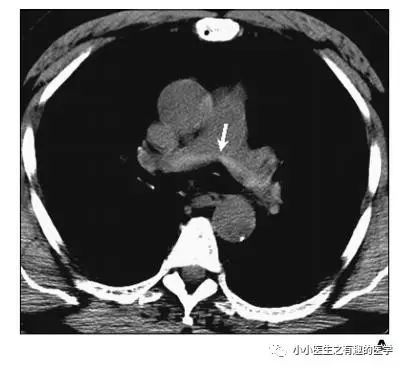

翠花上菜,学者上图。

发现嫌疑犯,立即逮捕。

增强CT对比,一目了然。

上面的患者,增强CT放大了。

下面是另外一个